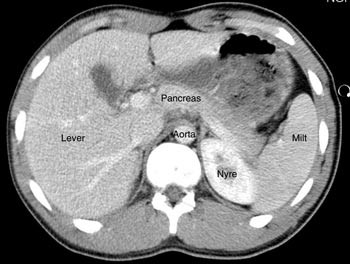

Pasient 2. En 20 år gammel mann ble utsatt for en trafikkulykke. Han var komatøs og ble intubert på skadestedet. CT-undersøkelse ved Ullevål universitetssykehus viste venstresidig pneumothorax og costafrakturer. I milten forelå en laserasjon kaudalt (skadegrad III), men normale funn i hilusnivå (e-fig 4). Pasienten ble observert og overflyttet til lokalsykehus etter tre dager. Seks dager etter traumet ble det gjort en CT-kontroll med arteriell kontrastfase. Denne viste en tilkommet, høytattenuerende lesjon ved milthilus, forenlig med et pseudoaneurisme (e-fig 5). Pasienten ble flyttet tilbake til Ullevål universitetssykehus hvor det ble utført angiografi med embolisering (e-fig 6). Ultralydkontroll samme dag viste opphørt sirkulasjon i lesjonen. Tre dager senere ble pasienten utskrevet.

I litteraturen er det beskrevet redusert sensitivitet og spesifisitet for pseudoaneurismer ved CT-undersøkelse sammenholdt med angiografi (8), men undersøkelsene er som oftest kun gjort i venøs kontrastfase. I flere studier er det benyttet forsinkelse fra kontrastinjeksjon til bildeopptak på mellom 70 og 85 sekunder som tilsvarer sen eller venøs kontrastfase (1, 9, 10). CT-bildene fra undersøkelsen av pasient 1 illustrerer at dette kan vanskeliggjøre diagnostikken. I tillegg er det viktig å vite at vaskulære lesjoner kan presentere seg forsinket. Det viser bildene av pasient 2. CT-undersøkelse i arteriell og venøs fase etter 5 – 7 dager i tillegg til undersøkelse ved innkomst er derfor anbefalt (2, 6).